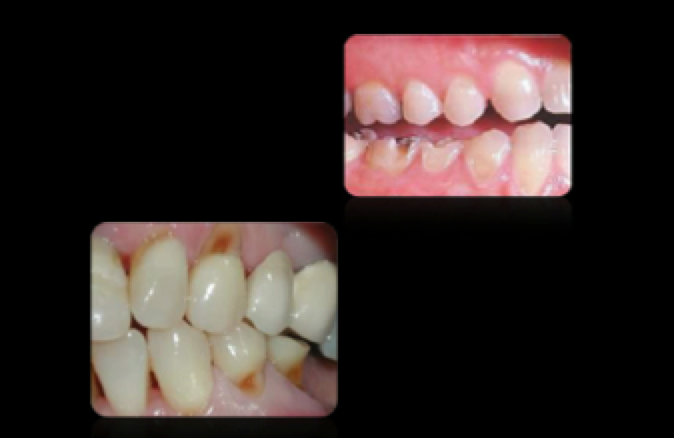

Active Lesion

Inactive Lesions

Inactive White Spot Lesion—–reversible & stable

Differential Diagnosis

—loss of tooth structure

Decalcification

Fluorosis